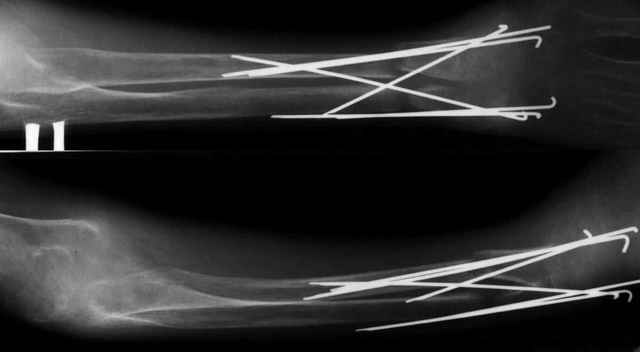

A male 23 y.o. many years sustained severe osteoporosis with multiple fractres of long bones and ribs. Last 4 years was not able to leave chair. Some x-rays attached. What may cause the situation? Juvenile osteoporosis should have been recovered spontaneously to date. What lab research is needed? What is most likely diagnosis? Can such fractures be treated more aggressively? What medications can improve bone quality? Biphosphonates? Somatotropin?